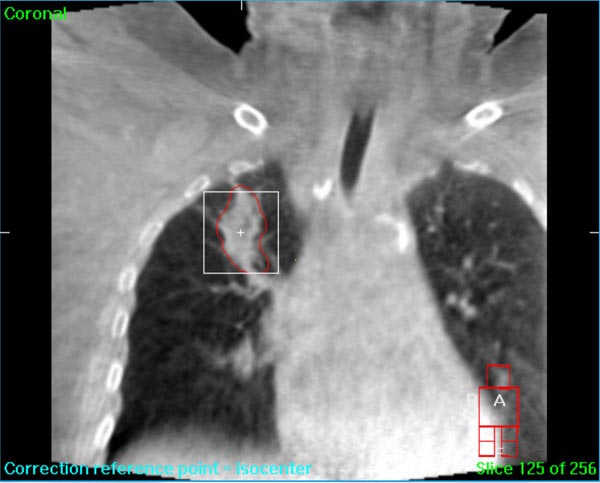

We understand that a cancer diagnosis can be scary, which is why Florida Center for Breast Conservation is dedicated to compassionate care and state-of-the-art technology. Florida Center for Breast Conservation uses the Elekta Synergy® machine, a digital accelerator for advanced image-guided radiation therapy (IGRT). It is the only all-digital treatment device in the world. This allows your doctor to view your tumor in real-time at the time of your treatment.

The 3-D high-quality images taken at the time of your treatment can be studied against your previous CT scans precisely and promptly to ensure that the doctors are treating your tumor as accurately as possible while greatly limiting any exposure to healthy tissue in the area.

Elekta Synergy® provides unparalleled clinical assurance to more aggressively treat tumors while keeping damage to surrounding healthy tissues to a minimum. Elekta Synergy®‘s precision accuracy reduces or eliminates the use of markers because clinicians can view soft tissue using Elekta Synergy®‘s VolumeViewTM. The low-dose imaging proficiency helps minimize the side effects of radiation therapy by decreasing the margins previously set to account for the unpredictability of target location, movement, and dimensions.